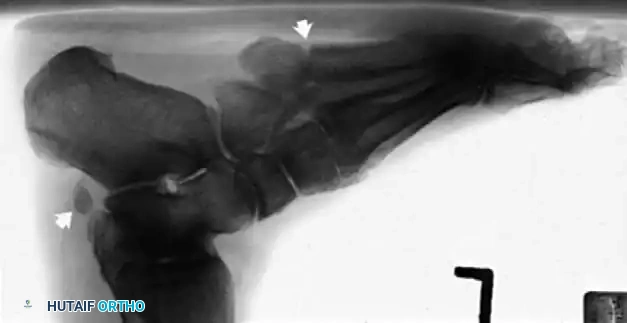

Imaging Modalities

Radiographic examination is indicated to assess for instability, osseous avulsions, and structural alignment. Plain films must be inspected carefully for bone densities in adjacent soft tissues, such as a "fleck sign" indicating SPR avulsion, or proximal migration of the os peroneum indicating a peroneus longus rupture.

While bone scans and computed tomography (CT) can be helpful for osseous pathology, Magnetic Resonance Imaging (MRI) and dynamic ultrasound are the gold standards for soft tissue evaluation. Grant et al. demonstrated the high sensitivity and specificity of ultrasound for evaluating peroneal tendon tears, allowing for dynamic assessment of subluxation. MRI provides excellent visualization of tenosynovitis, tendon morphology, and longitudinal split tears.